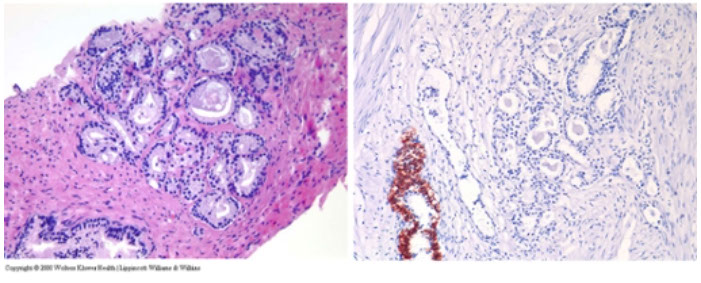

Triple cocktail stain c p63 (nuclei brown), HMWK (cytoplasm brown) and AMACR (red). B9 glands (lower left) have basal cells labeled c HMWK and p63. Cancer c AMACR positivity shows brown staining of scattered tumor cells in a nonbasal cell distribution. Note positive tumor cells show cytoplasmic staining only, indicating nonspecific positivity for HMWK and not p63

Triple immunostain in the diagnosis of prostate adenocarcinoma. A small focus of prostatic adenocarcinoma is showing in the lower part of the core (A) and highlighted by overexpression of a-methylacyl coenzyme A racemase (red chromogen) and lack of basal cells demonstrated by negative immunostain of p63 and high-molecular-weight cytokeratin (HMWCK) (B). Adjacent benign glands (B) show basal cell stain for p63 (nuclear) and HMWCK (cytoplasmic) [6]